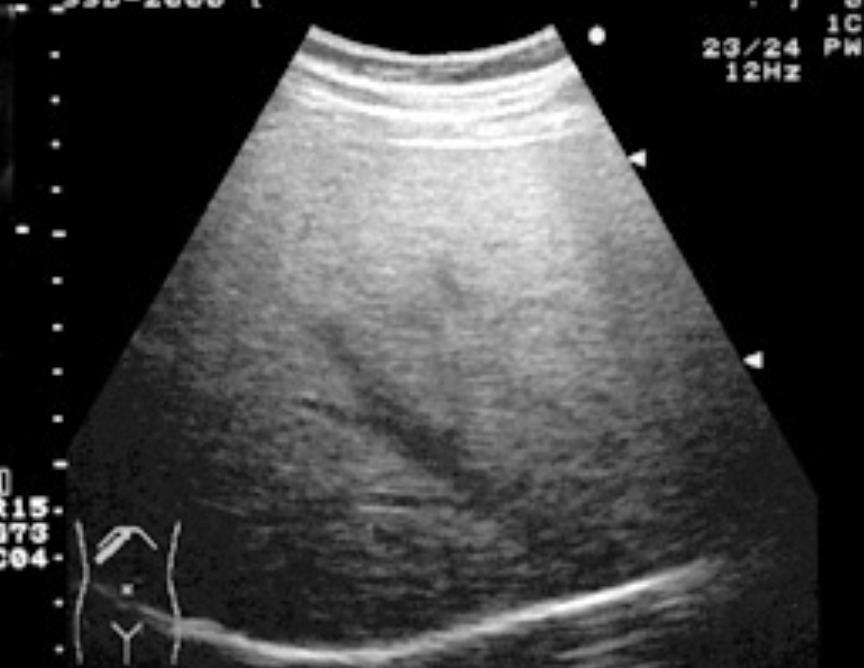

【高エコーの一例】

脂肪肝の症例でいわゆるbright liver。肝実質のエコーレベルは音波の散乱が高度なため上昇するが、逆に深部では音波の減衰のため暗く描出されている。

少しでも客観的に評価するために腎臓と一緒に描出して右腎実質に比べてエコーレベルが高くなっているかどうか見る。(肝臓が腎臓よりも明るく見えることを肝腎コントラストがあると表現する。)